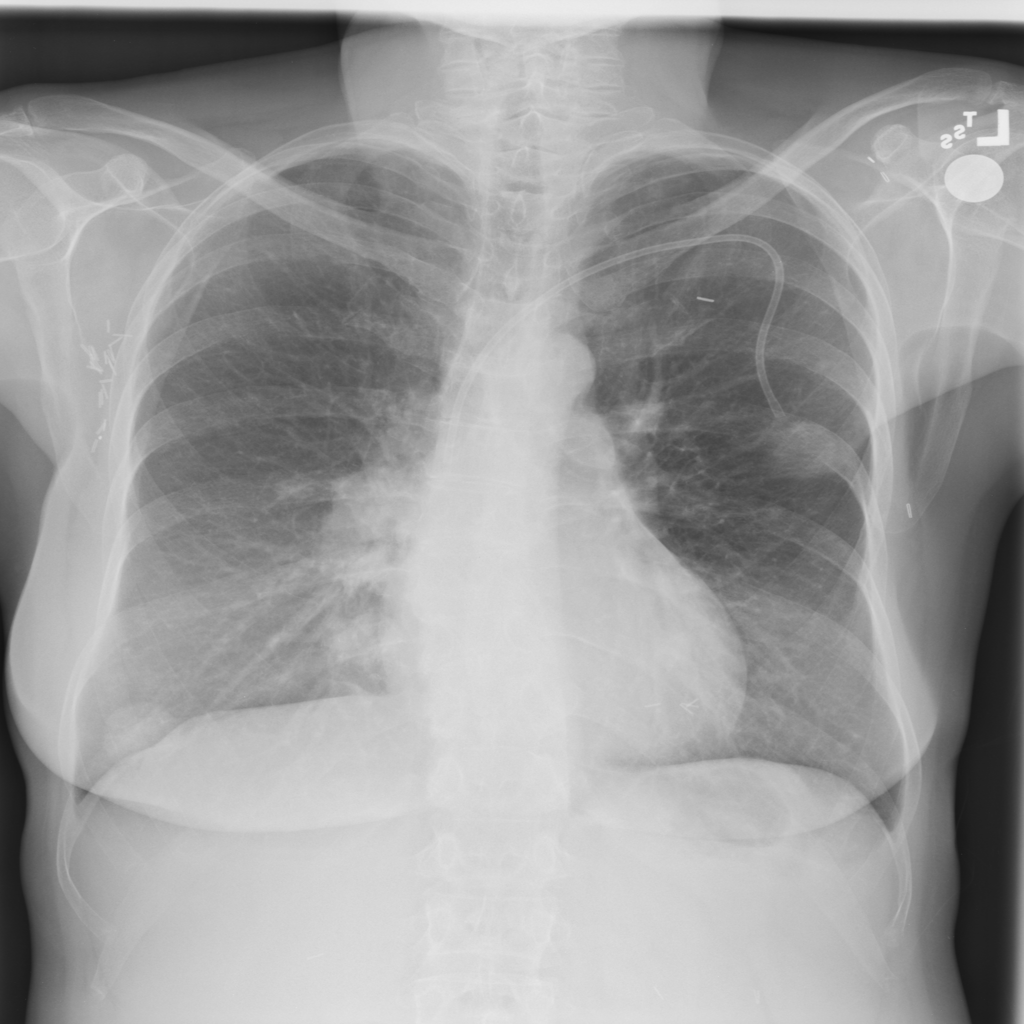

PAT-C0E5 · IMG-001Mass

PAT-C0E5 · IMG-001

PA